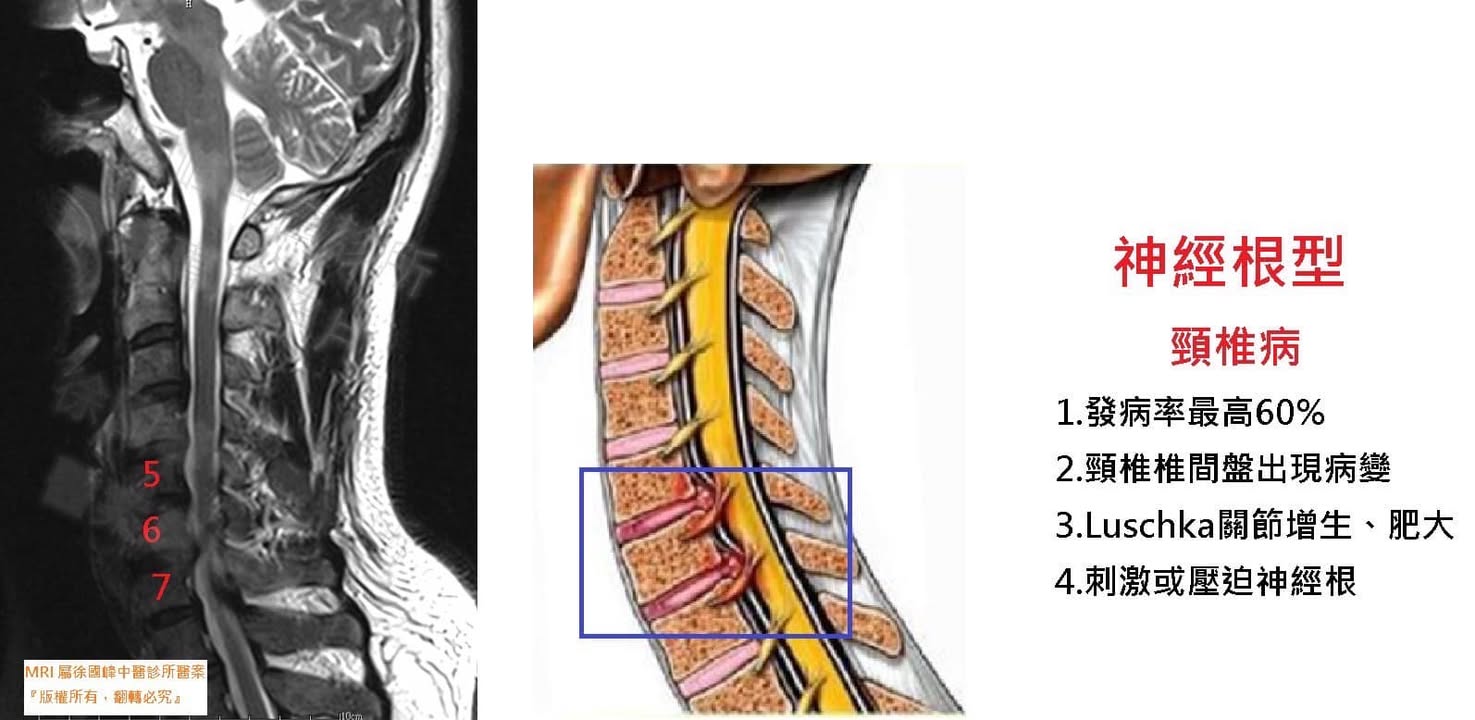

1.頸椎過直

2.右側C5C6;C6C7神經根型頸椎病

👉病因:骨質增生、軟組織變性、外傷

👉病變:椎間孔變窄椎間盤突出,四肢出現麻木、疼痛

👉病痛原理:頸神經受壓多見於第四~七頸椎處